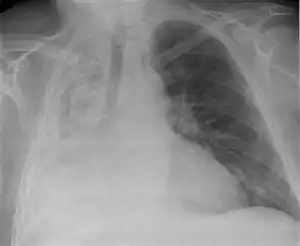

Compression (relaxation) atelectasis

It is usually associated with accumulation of blood, fluid, or air within the pleural cavity, which mechanically collapses the lung. This is a frequent occurrence with pleural effusion, caused by congestive heart failure (CHF). Leakage of air into the pleural cavity (pneumothorax) also leads to compression atelectasis.[12]